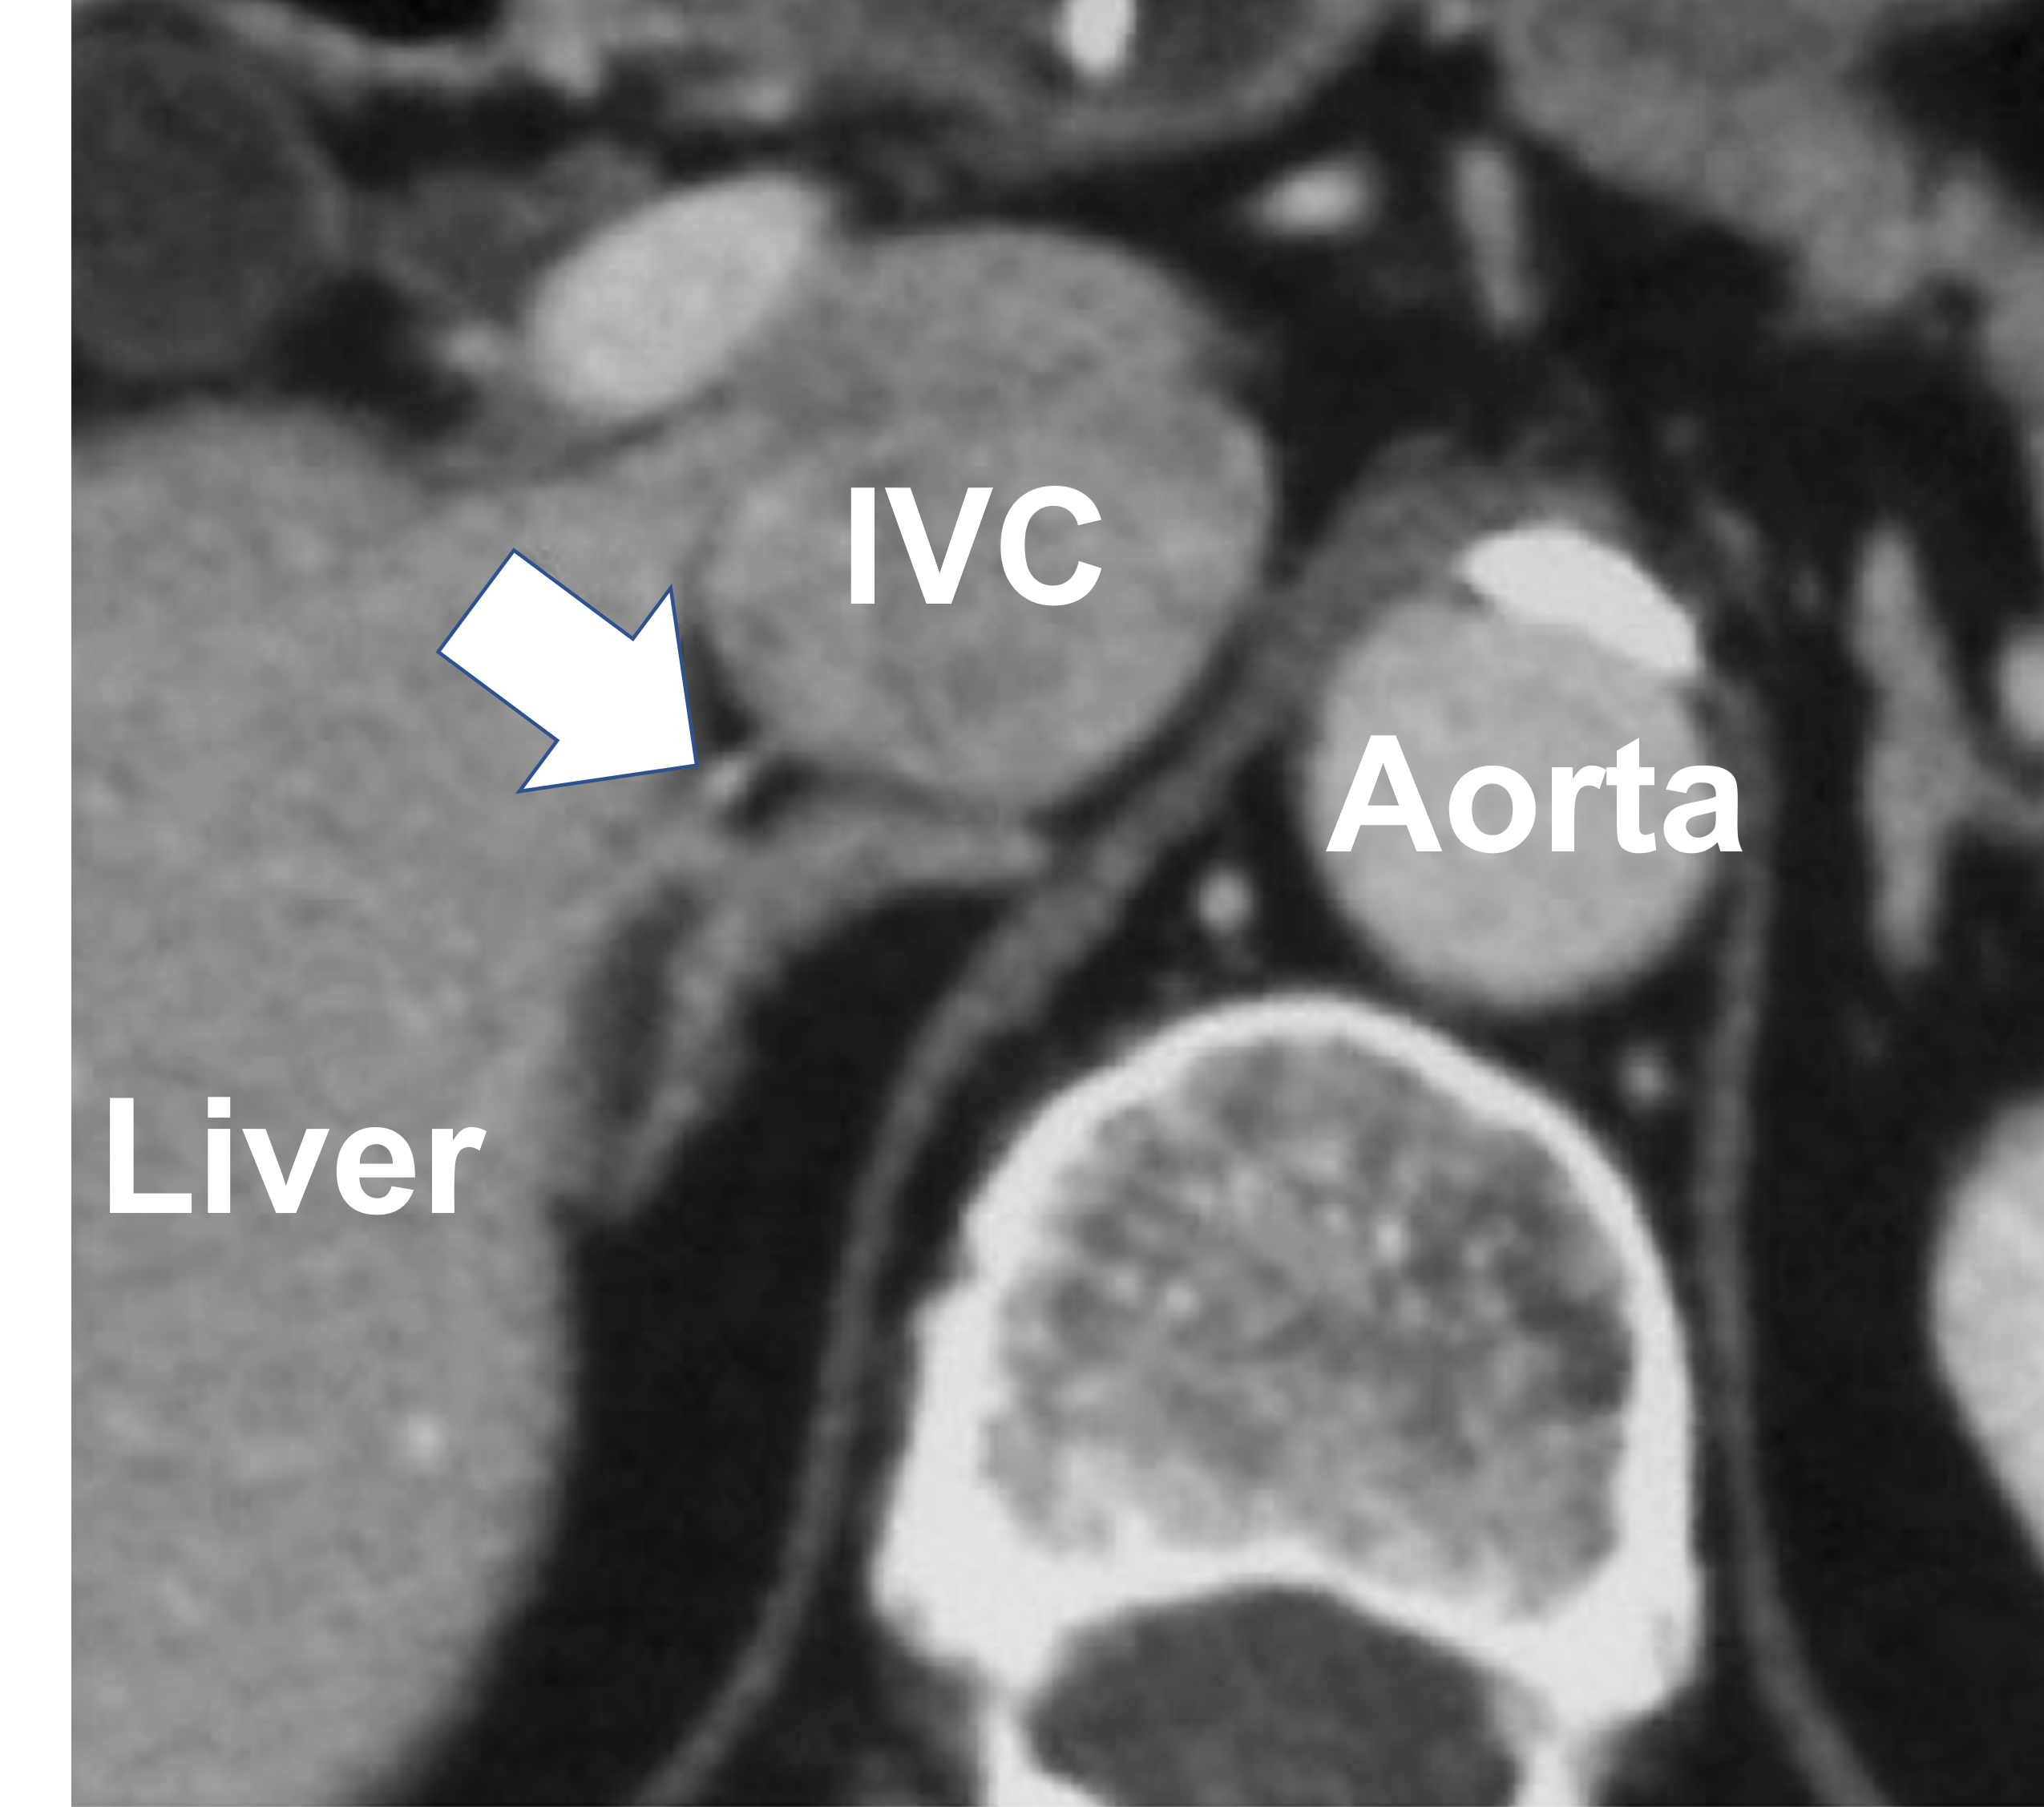

CT scan clearly shows the right adrenal vein (arrow) A special pre-procedure adrenal CT scan protocol developed by Dr. Carling and his radiology colleagues clearly identifies the right adrenal vein (arrow) draining into the inferior vena cava (IVC) It is very important to have a specific adrenal-protocol CT scan prior to adrenal vein sampling since it improves the technical success rate dramatically. The reason for this is that the CT scan gives very detailed anatomical information about the tiny adrenal veins, specifically the right adrenal vein. The CT scan guides the interventional radiologist during the procedure and allows him to accurately identify the tiny vessels. Dr. Carling and his radiology colleagues at the Carling Adrenal Center have developed a very specific pre-procedure CT scan protocol that dramatically improves the success rate of adrenal vein sampling. If your center does not offer an adrenal protocol pre-procedure CT scan in preparation of your adrenal vein sampling, chances are the success rate is very low and you should consider going elsewhere.